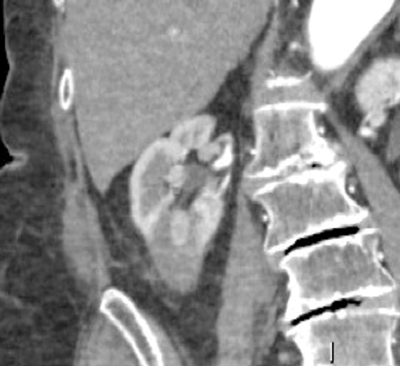

Residual tumour or locally recurrent tumour is most commonly depicted as an area of nodular enhancement at the tumour margin (Figure 4).

Figure 4: Nodular tumour recurrence within a lower pole ablation zone.